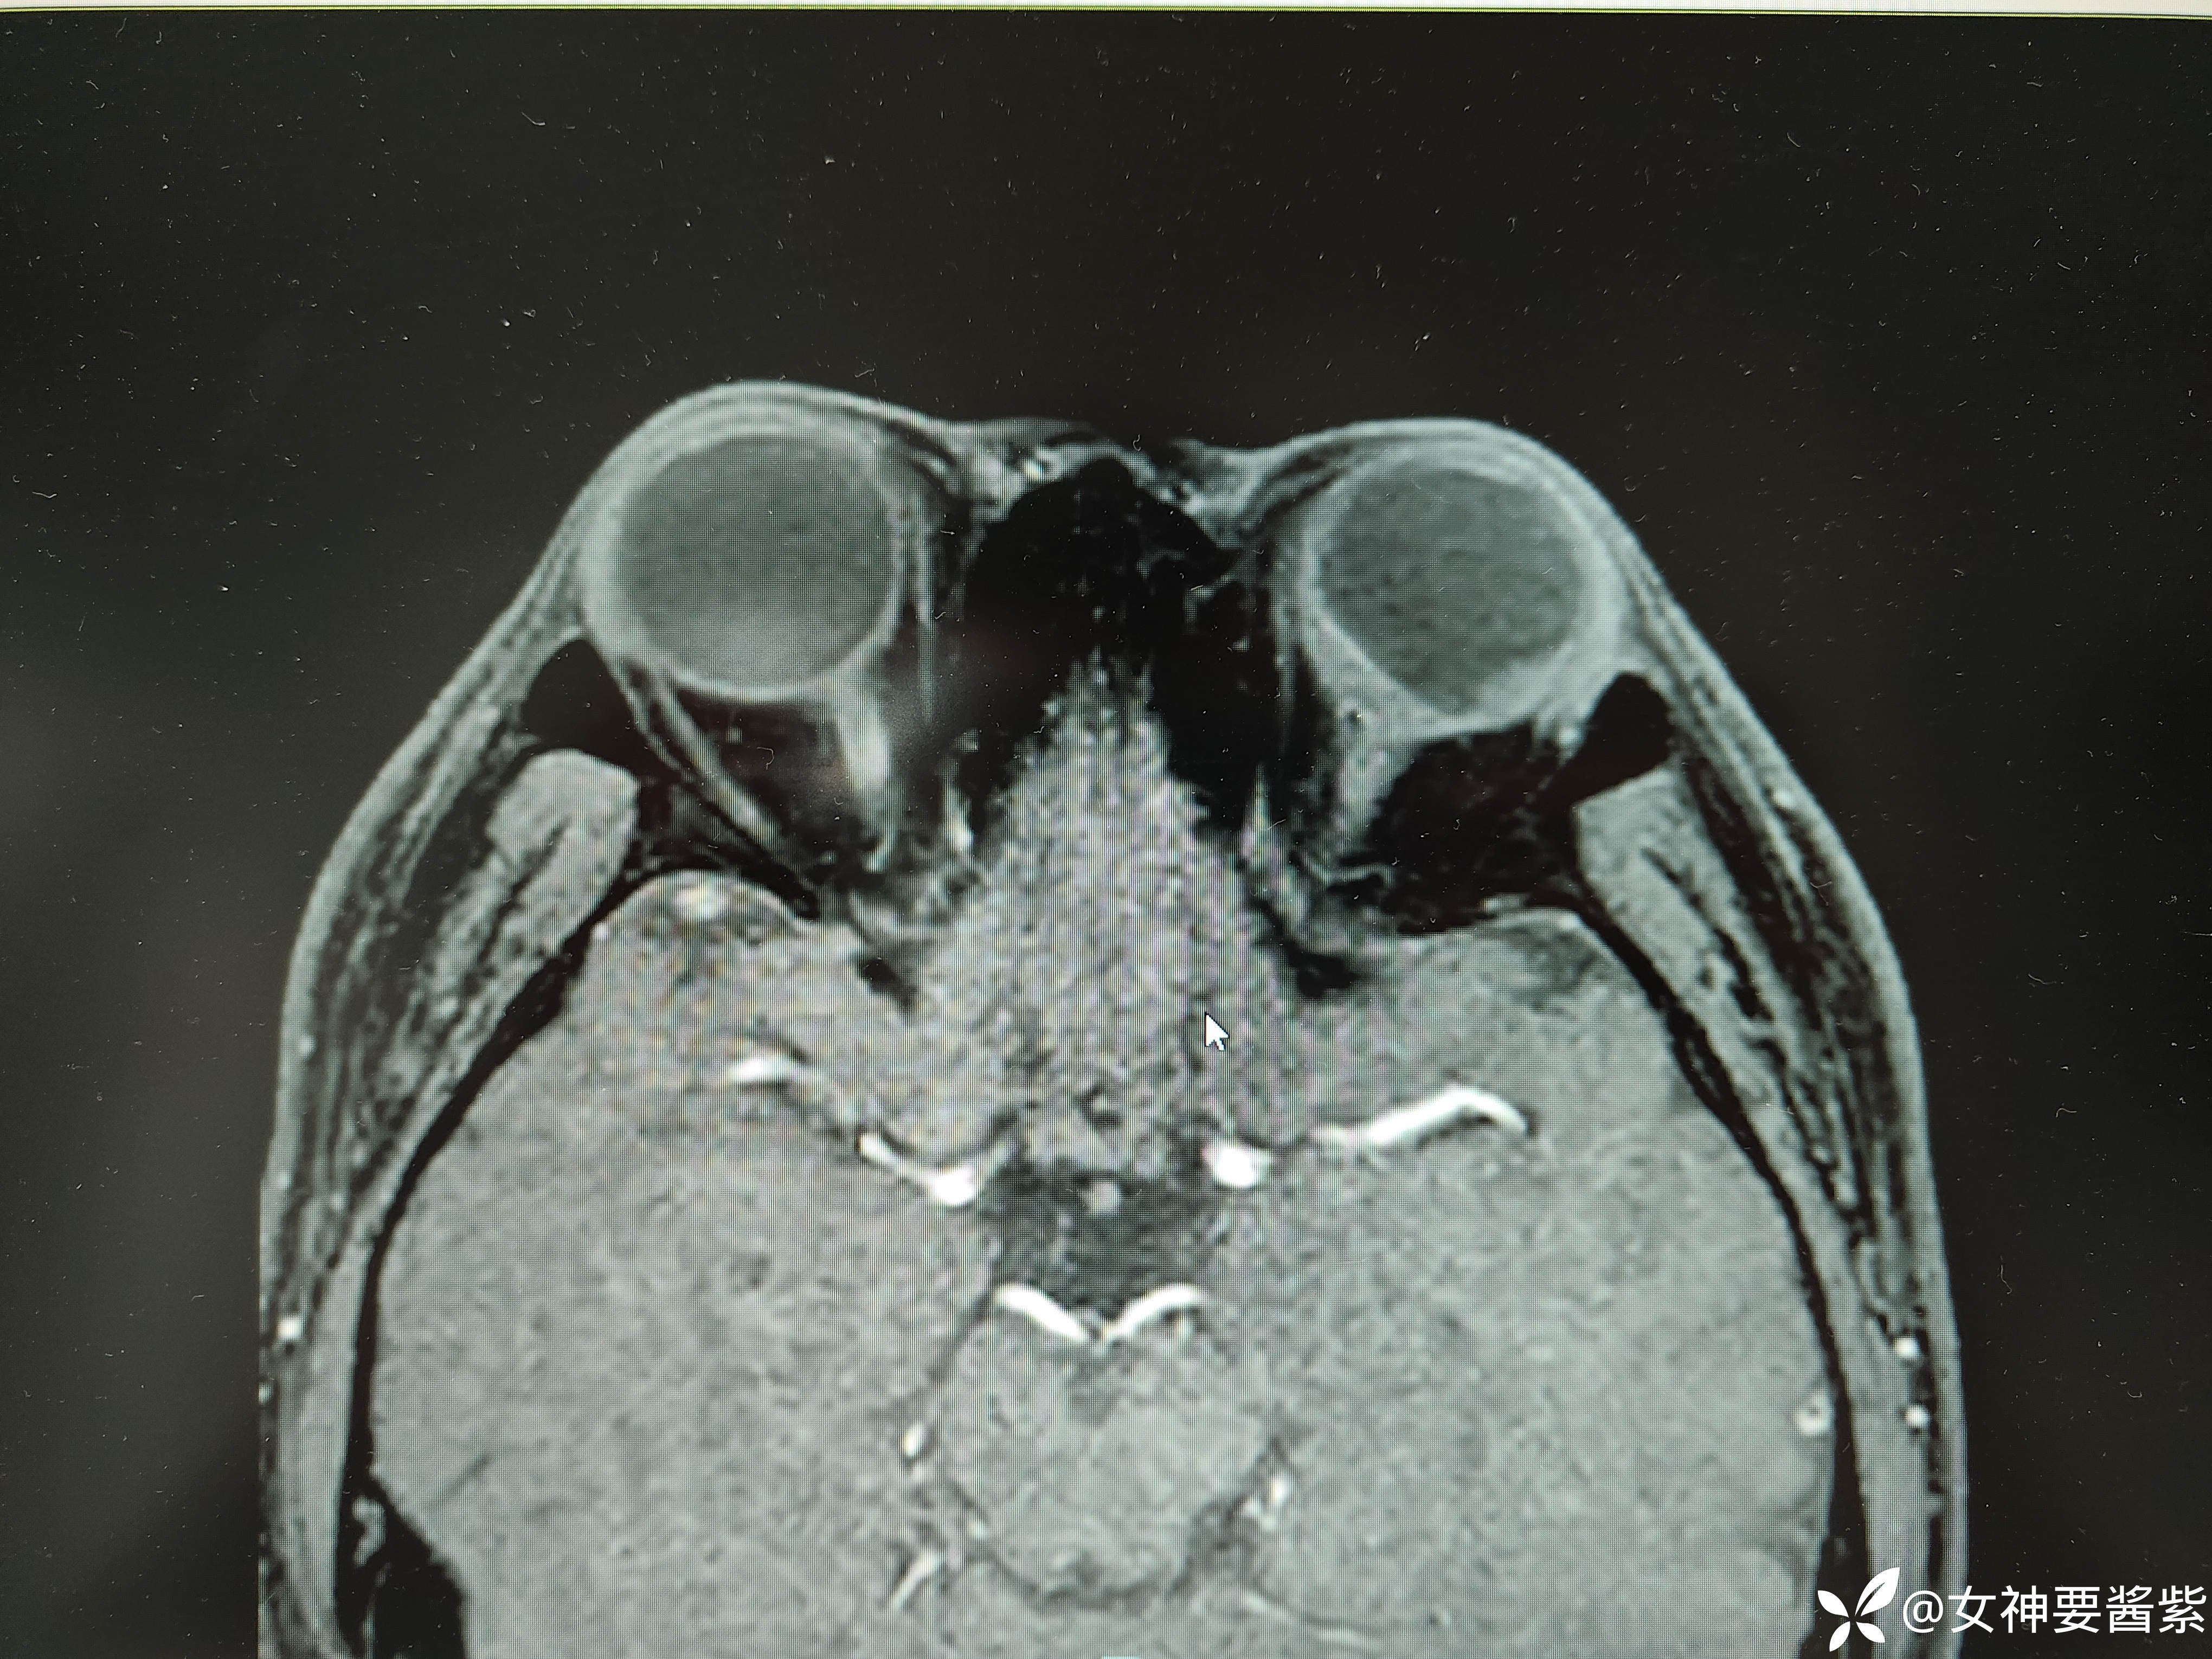

MR